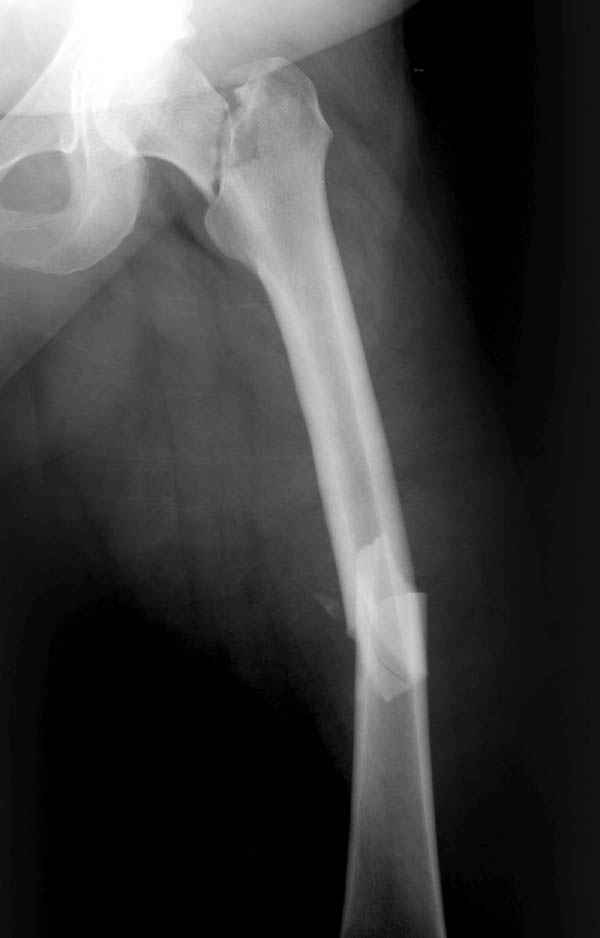

Имя     : ipsilateral neck shaft.JPG

Имя     : ipsilateral neck shaft nonunion.JPG

Несмотря на пессимистические прогнозы, у молодых

Представленные случаи доказательства тому, что еще

имеется резервы на восстановление даже у 5-6 месячных ложных суставов шейки.